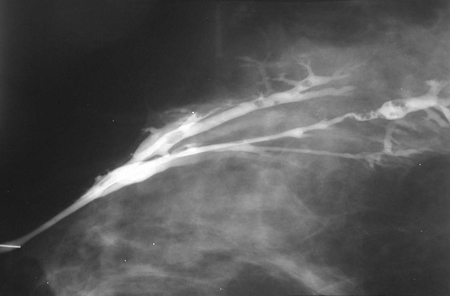

Breast papilloma

A bloody nipple discharge is typical of breast papilloma. This type of lesion can occasionally be detected as a mass within the breast. The growths often occur within the breast ducts (intraductal papillomas). These lesions are typically benign, but they can be associated with histological findings of atypia, papillary ductal carcinoma in situ (DCIS), or invasive papillary cancer.[Figure caption and citation for the preceding image starts]: Ductogram demonstrating multiple intraductal papillomasCourtesy of Dr Nancy Pile, University of Louisville; used with permission [Citation ends].